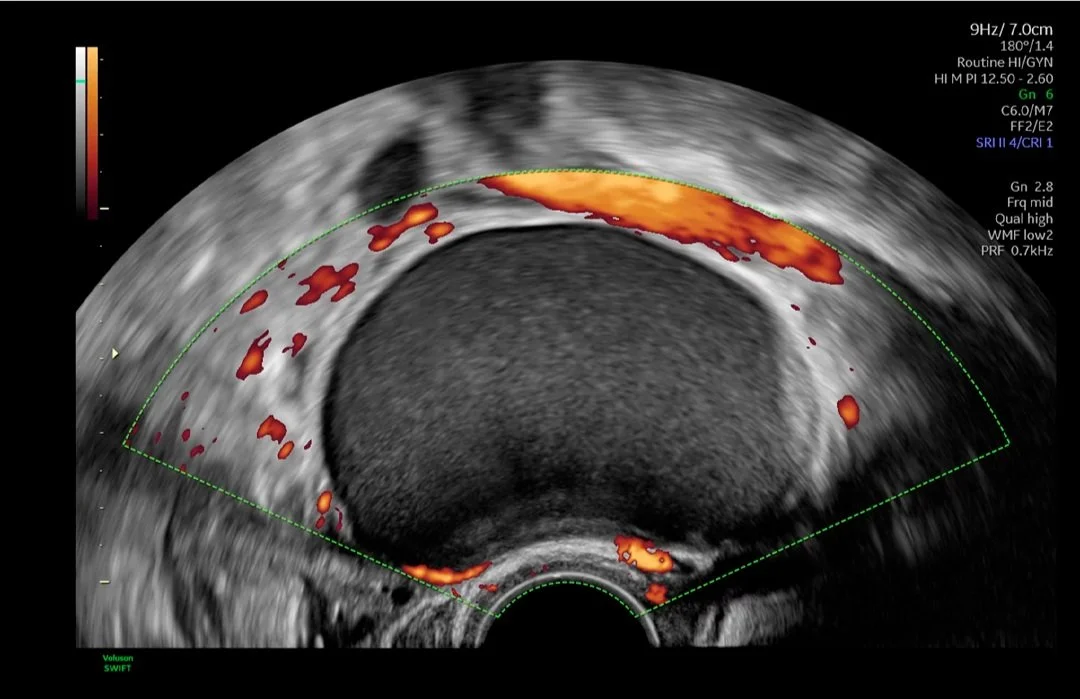

Ginecología

A menudo, la ecografía es la primera línea de defensa para diagnosticar afecciones ginecológicas. El dolor pélvico, el sangrado postmenopáusico, la disfunción genitourinaria y la infertilidad pueden ser síntomas confusos y preocupantes para sus pacientes. Necesitan respuestas y confían en su experiencia para obtener un diagnóstico y tratamiento precisos.

Medicina reproductiva asistida

Entendemos el impacto que tiene la infertilidad en la vida de sus pacientes y en su práctica. Por este motivo, los sistemas de ultrasonidos Voluson superan continuamente los límites de la adquisición de imágenes para ofrecerle herramientas sencillas e innovadoras que le ayuden a usted y a sus pacientes a vivir el sueño de un embarazo próspero.